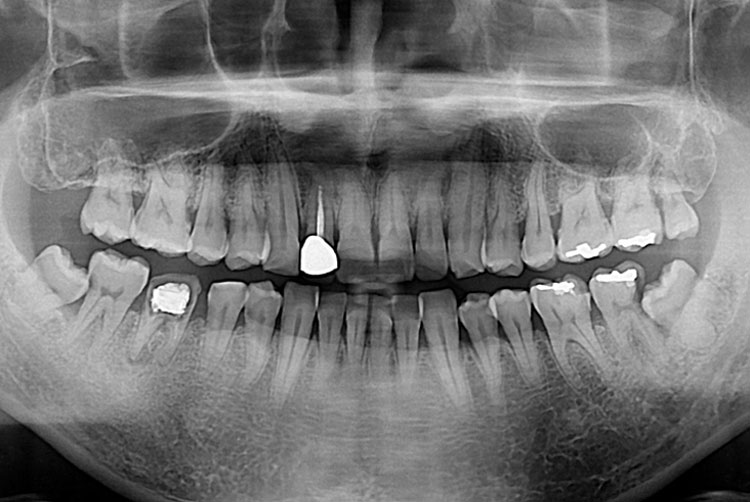

치료전 : 2017-08-17

엄윤득_후.jpg

세종치과는 많은 환자와 다양한 케이스를 바탕으로 항상 편안한 임플란트 수술을 제공하고자 노력하고,

오래동안 튼튼히 쓸 수 있는 임플란트 수술을 가장 큰 목표로 삼고 있습니다.